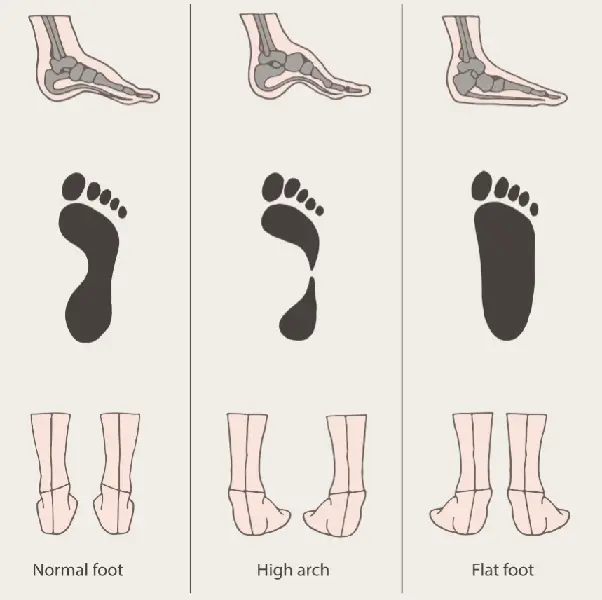

Foot Postures: What It Means for Your Feet?

Flat Feet and High Arched Feet | Things to Know – Custom Rehab

Understanding Foot Types and Managing the Adolescent Athlete